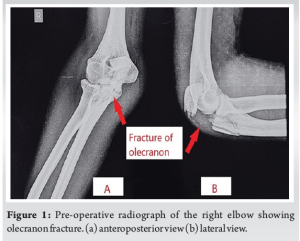

The right elbow’s displaced comminuted olecranon fracture was identified by a normal radiograph as shown in (Fig. 1).

Case Report: In our case report, a male in his 20’s came to the outpatient department with complaints of pain in the right elbow since 1 day following a fall from a bike. He also reported that he was unable to fully extend his right elbow. After a plain radiograph, a right displaced comminuted olecranon fracture was suggested. He underwent a pre-anesthesia checkup and standard laboratory testing before being taken for surgery. Open reduction internal fixation with fragment-specific plates was done. An above-elbow slab in the extended position was applied post-surgery and continued for 14 days. Elbow range of motion physiotherapy was started in accordance with tolerance, and the patient responded favorably to surgery.